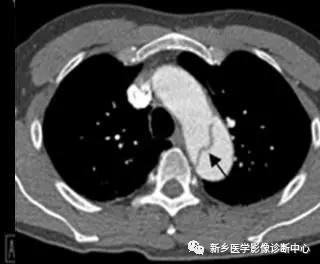

18 肺动脉栓塞

文章图片